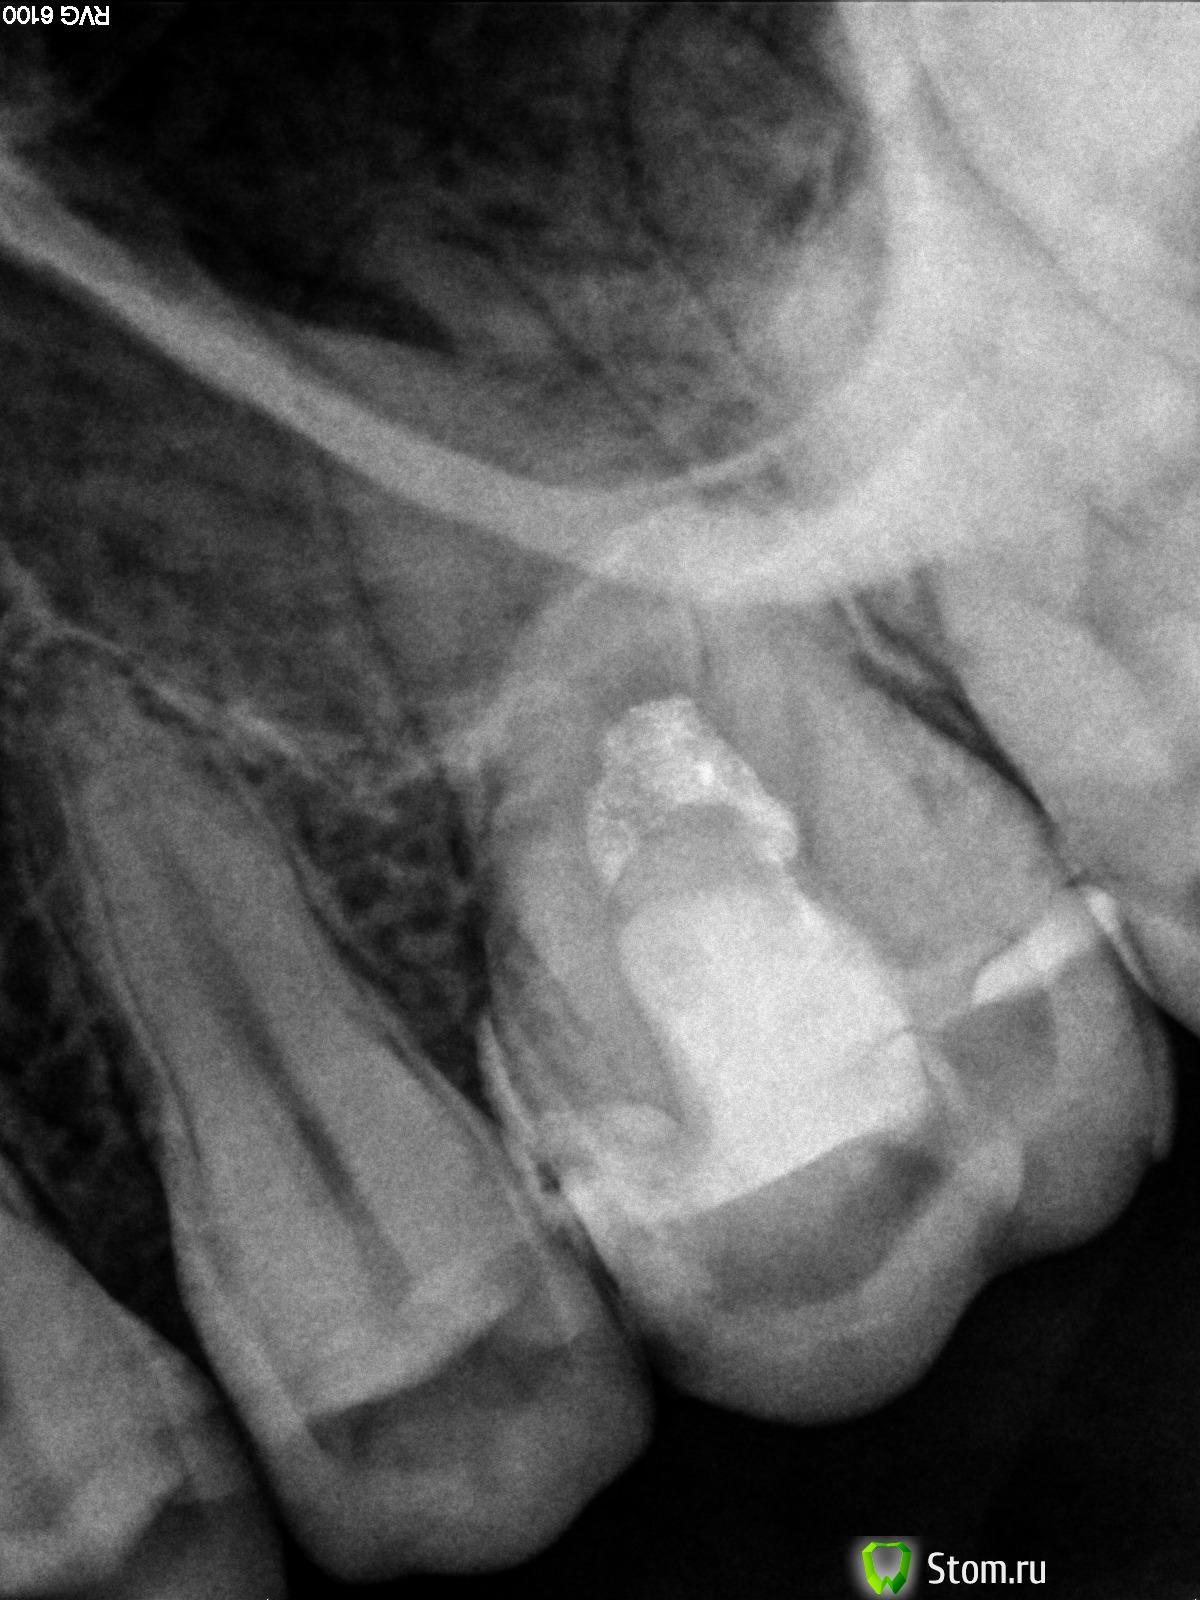

kurt Опубликовано 25 февраля, 2012 Автор Поделиться Опубликовано 25 февраля, 2012 (изменено) ув. juli63, снимки прилагаю ниже: на 1м, как понятно, это до лечения - удаления части нерва, на 2м это уже после установки постоянной пломбы - настоящее состояние зуба. ув. dmitrySH прав, что на снимке, если я не ошибаюсь, то эта поперечная трещина не видна. Изменено 25 февраля, 2012 пользователем kurt Ссылка на комментарий

kurt Опубликовано 24 февраля, 2012 Поделиться Опубликовано 24 февраля, 2012 (изменено) доброго времени суток! речь пойдет о моем шестом зубе сверху слева. - больше 6 лет назад мне его запломбировали и на протяжении этого срока он с разной периодичностью незначительно побаливал сам собой, невлияя на воздействия еды, воды... но в начале этого года зуб ныть стал значительно, отвлечься не удавалось. обратился к замечательному стоматологу, у которого лечу зубы последнии лет 10, и всегда работой его доволен! когда, кстати лечиил эту 6ку, то в клинике его заменял другой врач, который запломбировал 6ку. доктор сделал снимок (на руках нету, хранится в электронном архиве врача) и решил срезать часть нерва. анастезия, сверление, удаление часть нерва, временная пломба. зуб ныть перестал и все вроде бы хорошо, но день на 5-6 неудачно откусил твердую пищу и почувствовал такое ощущение, что пломба якоба просела внутрь... часть верхней пломбы слетело, конечно. далее следует обращение к врачу, который снимает временную пломбу и сообщает мне, что весь мой зуб поперек пронизывает микротрещина... ставит "мощную" пломбу, пломбируя также зуб с внутренней стороны полости рта. при манипуляциях с бурмашиной никакой боли не ощущал (чистка и бурение было без анастезии). и после уже начались танцы с бубнами... при механическом воздействии еды, холодного - начались боли... выждали с врачом более 3х недель, на механическое воздействие боли уменьшились, но пить холодное вообще не могу - сильная боль. врач после моего очередного посещения выносит вердикт: что т.к. весь зуб поперек пронизывает микротрещина, которая и является проводником холодного до пульпы, что вызывает сильную боль, то при удалении всего нерва - зуб скорее всего весь разрушится и скорее рано, чем поздно... поэтому лучше сразу его удалить с корнем и ставить имплант, что огорчило меня... ведь я шел с настроем, что можно будет корень сохранить и поставить штивт, но доктор аргументировал трещиной и что корень надо тоже удалить. скажу сразу, что врача уважаю и считаю его очень хорошим специалистом, но всегда хочеться услышать еще мнения профильных докторов! здоровье то одно... как и зуб. поэтому прошу Вас высказаться, прокомментировать, дать свою оценку ситуации и ее возможное решениею! заранее выражаю благодарность всем, кто поможет советом! СПАСИБО!!! Изменено 24 февраля, 2012 пользователем kurt 1 Ссылка на комментарий